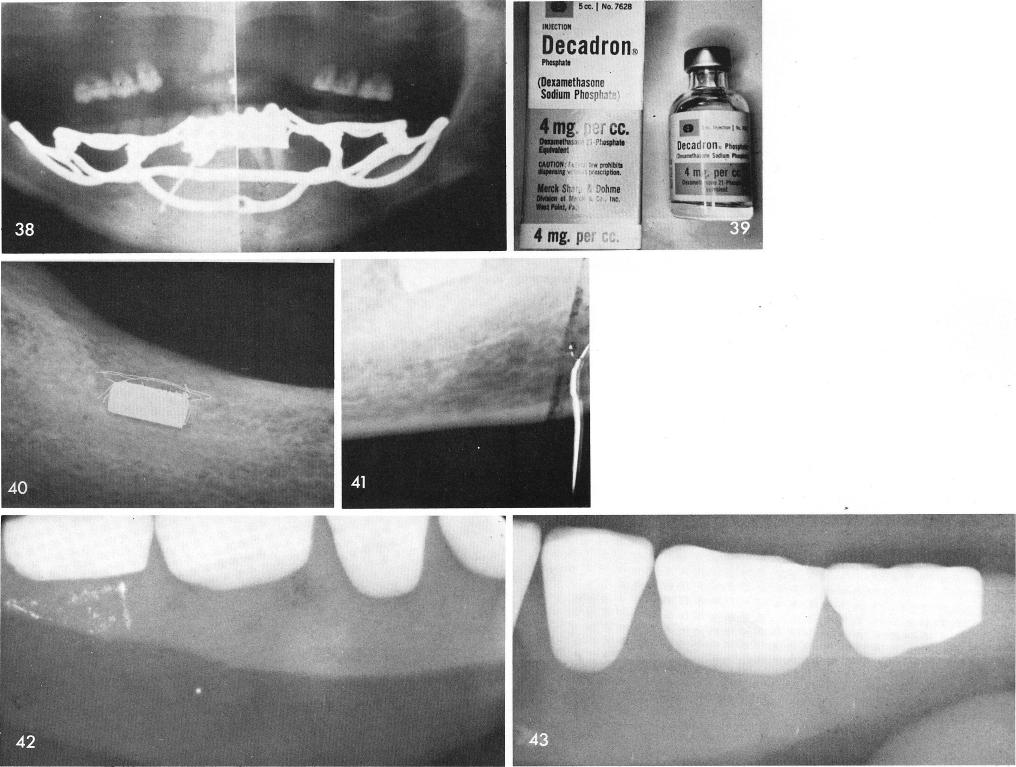

was processed, fig. 34, it was placed in position, figs. 35, 36, and x-rays were taken, figs. 37, 38. One and a half to two cc of Decadron Phosphate intramuscularly after surgery seems to work very well in reducing or eliminating the swelling sequellae, fig. 39.

A very interesting case came into my office in the early 1960s complaining of a loose fitting denture with constant sore spots. Upon radiographic examination, magnets were revealed in the posterior portion of each side of her mandible, figs. 40, 41. Upon examining the lower denture, seeing no attracting magnets I decided to radiograph the teeth. They revealed no magnets, figs. 42, 43. Upon further questioning the patient, she claimed that her constant visits to her dentist complaining of pain posteriorly gradually caused all of the denture magnets to be ground away, thus establishing that even a denture with attracting magnets is still tissue borne and the patient still suffers from denture sore spots.

1 Decadron Phosphate intramuscularly after surgery reduces the swelling